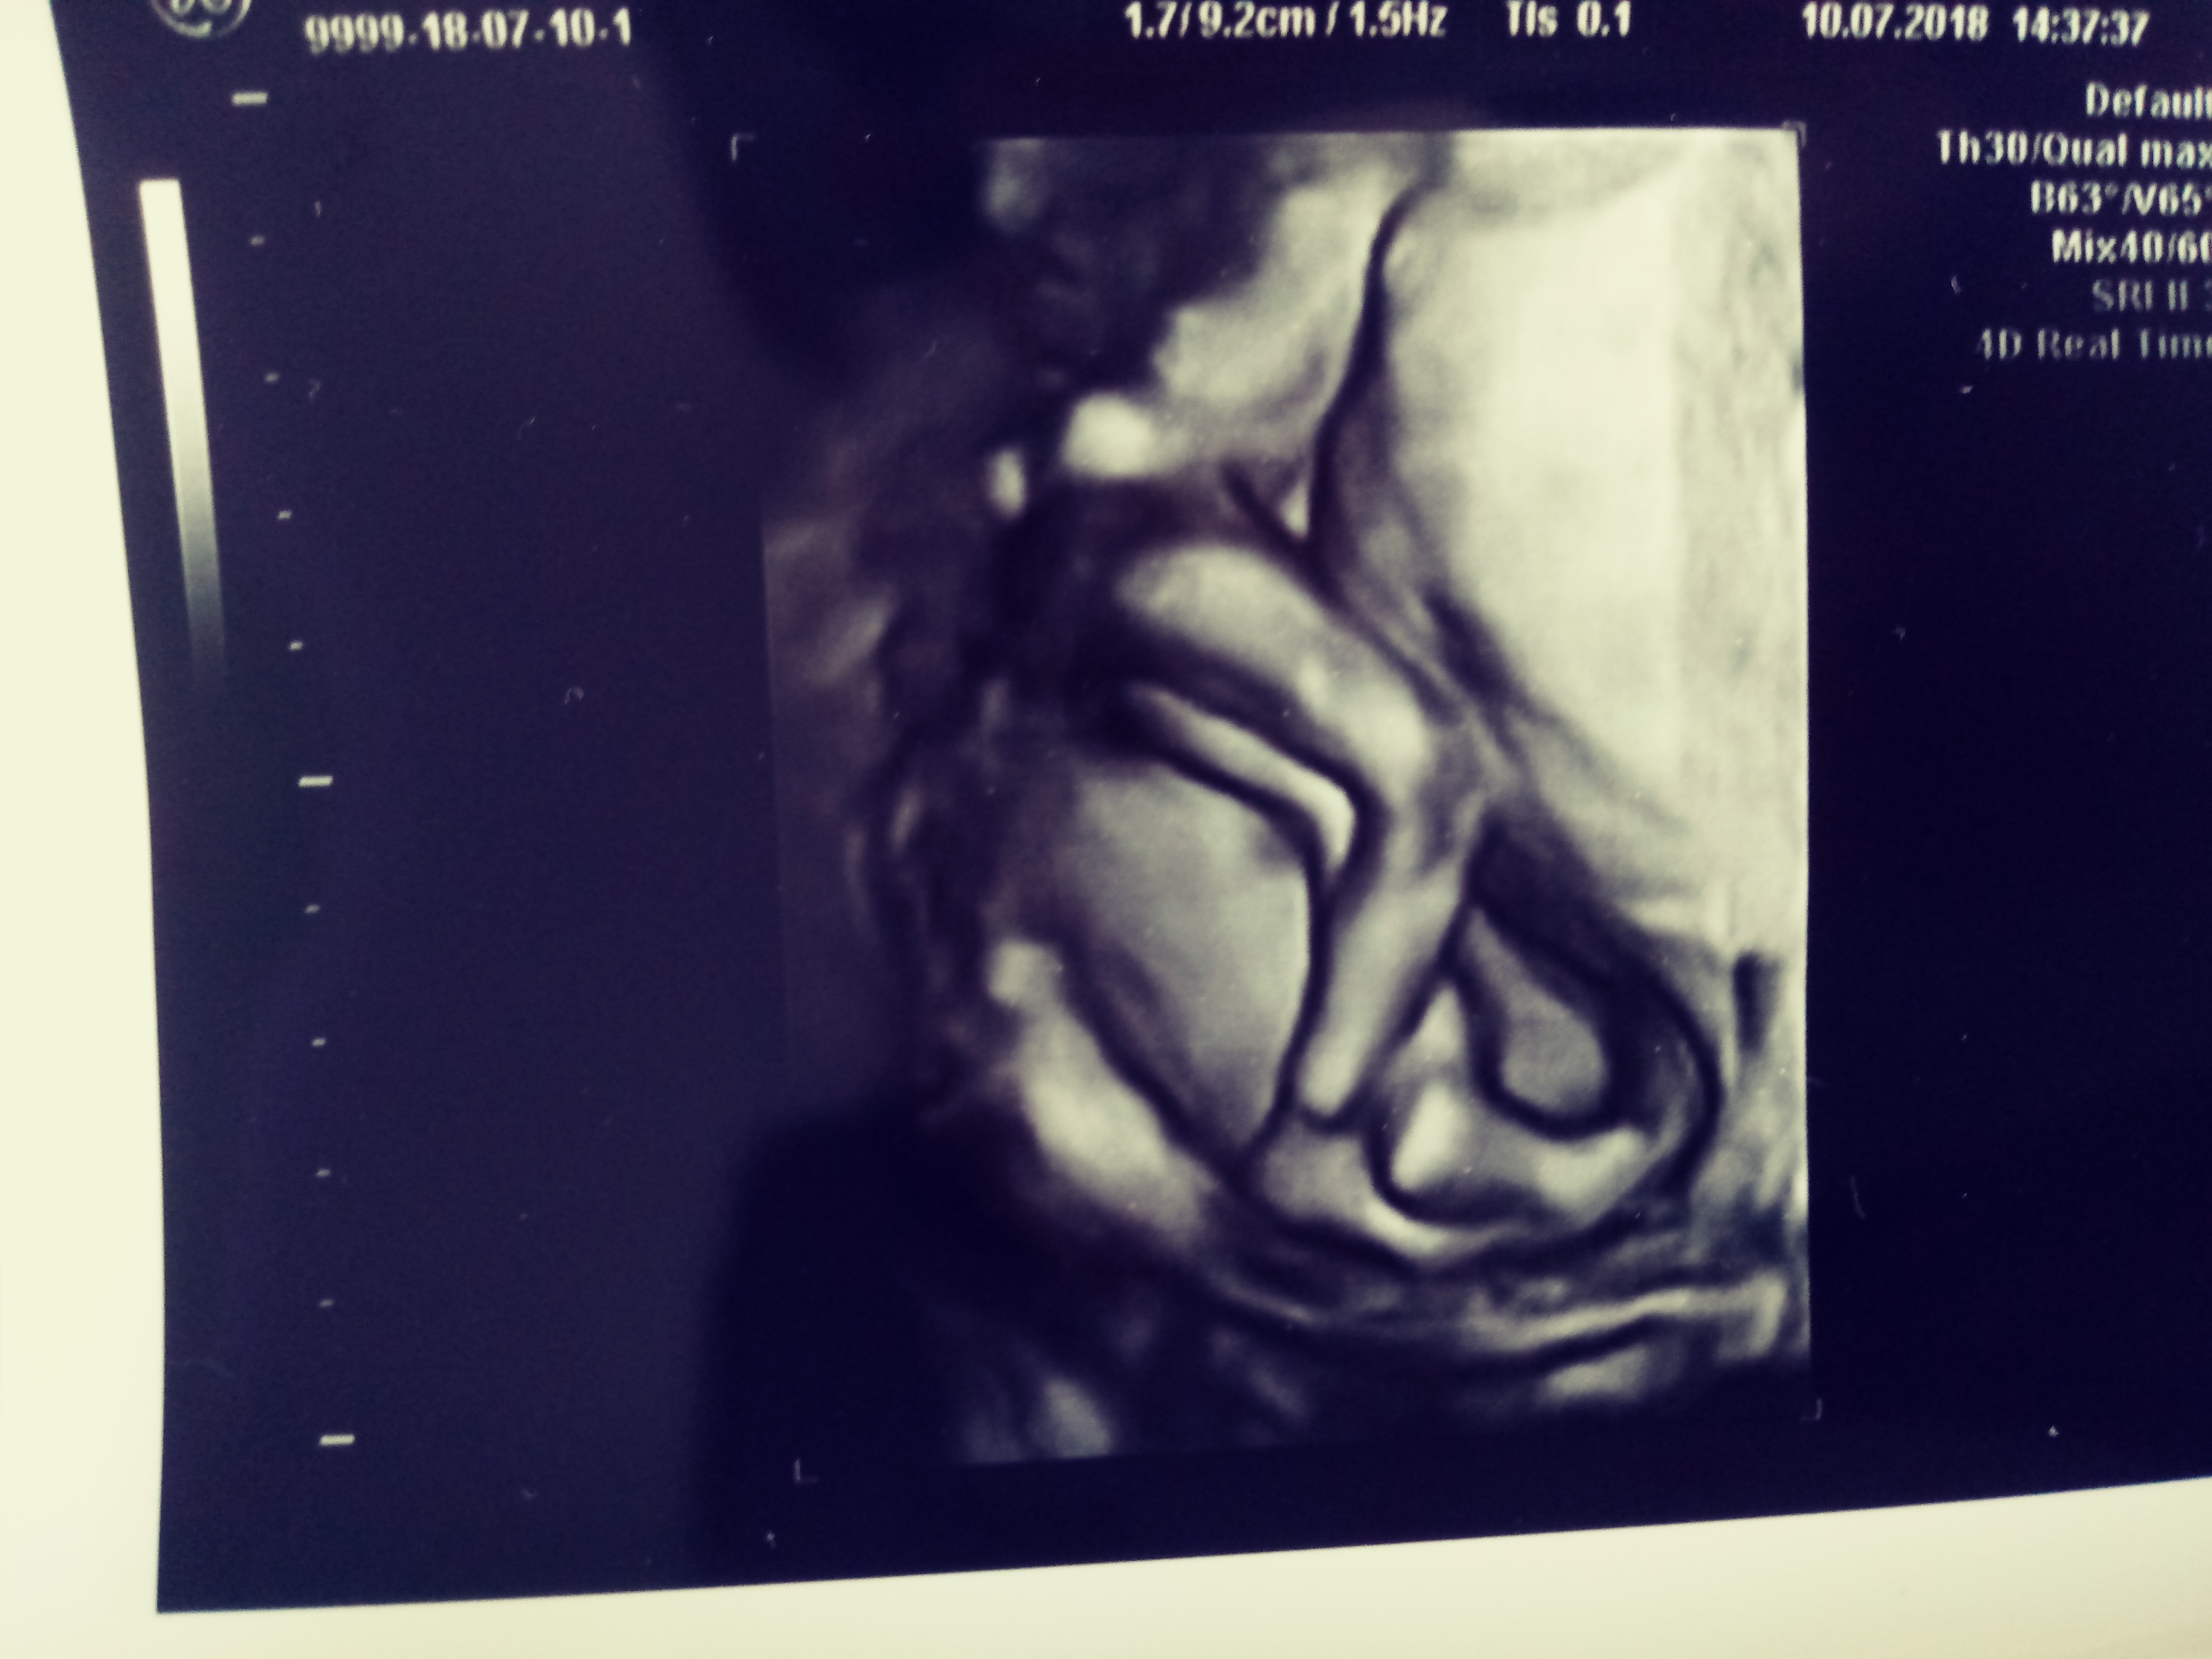

No ciekawa jestem co w ich mniemaniu oznacza pełen zestaw badań.... Zważywszy na fakt że mocz sprawdziła położna I jet ok, krew badana w czwartek i choć wszystkiego na granicy to jednak w normie.... Jeśli to nie będzie ginekologiczne I usg to ja już nie wiem sama....To dobrze i jak pojedziesz nie daj sie puscic torbami tylko niech Cie wybadaja szyjke i o przepływy zapytaj czy robią